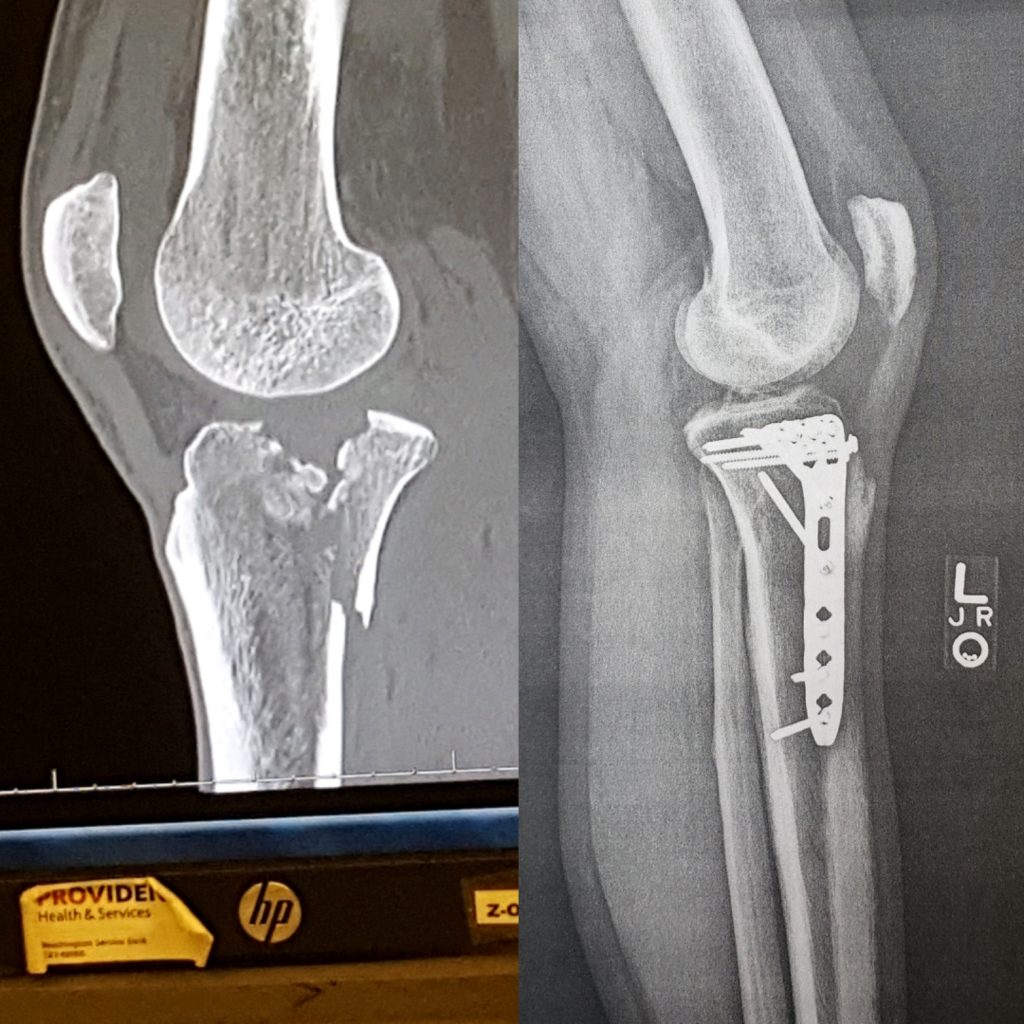

On Friday, June 14th, at the lovely hour of 1:30am, I was curled up in the fetal position on the floor of the MGM Grand in Las Vegas clutching my knee. I had just suffered an accident that shattered my tibia.

I would need reconstructive surgery and almost 4 months bed rest to recover, plus MONTHS of physical therapy to regain capacity. And even then, it was obvious that it would be dangerous for me to attempt to push my body to the limits anymore.